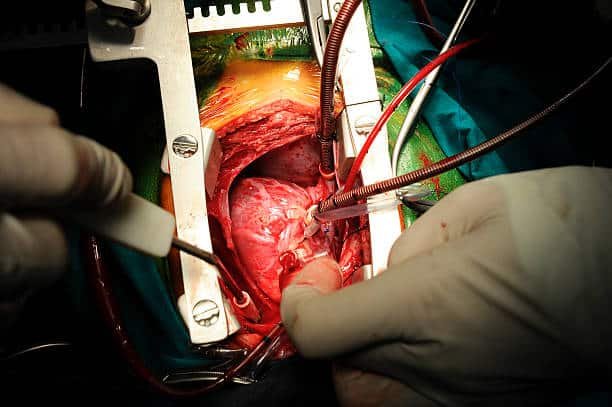

تُسمّى جراحة القلب المفتوح للاطفال بجراحة القلب التقليديّة، وهي عمليّة يتم فيها فتح الجدار الصدريّ لتنفيذ جراحةٍ في عضلات القلب أو صمّاماته أو شرايينه، حيث يقوم الجرّاح بشقّ عظم القصّ أو الجزء العلوي منه، وبمُجرد الوصول إلى القلب يتم وضع جهاز قلب-رئة اصطناعيّ ليحلّ محلّ القلب ويقوم بوظيفته التي تتمثّل في ضخّ الدّم إلى جميع أجزاء الجسم، ويسمح هذا الجهاز للجرّاح بإجراء العمليّة في القلب المُتوَقِّف عن العمل والذي لا يتدفّق الدّم من خلاله،

وأصبح من المُمكن إجراء هذه العمليّة من خلال شقوق صغيرة بين أضلاع القفص الصدريّ عوضاً عن الشقّ الكبير المُعتاد في عظم القصّ، وتسمّى بالجراحة طفيفة التوغّل، من الممكن استخدام جهاز قلب-رئة اصطناعي في هذا النّوع من الجراحة أو الاستغناء عنه، ولذلك تُعدّ التّسمية بجراحة القلب المفتوح للاطفال غير دقيقة في بعض الأحيان.

- يُفتح مركز الصّدر (6-8 إنش )، ثم تُشقّ عظام القصّ ويُفتح القفص الصدريّ حتى يتمّ الوصول إلى القلب، ثم يُوصَل جهاز قلب-رئة الذي يقوم بوظيفة القلب في ضخّ الدم إلى جميع أجزاء الجسم بعيداً عن القلب، ثم تُجرى العمليّة المطلوبة في القلب.

- بعد إجراء جراحة القلب المفتوح يُعيد الجرّاح تدفُق الدّم عبر القلب، ثم يعود القلب للعمل بشكل تلقائيّ، لكن في بعض الأحيان قد تُستخدَم صدمات كهربائيّة خفيفة لإعادة تشغيل القلب، ثم يُزال جهاز قلب-رئة. تُستخدَم أسلاك خاصّة ودائمة لإغلاق عظم القصّ، ثم يُغلَق جلد الصّدر بالغُرز، ويُزال أنبوب التنفّس.